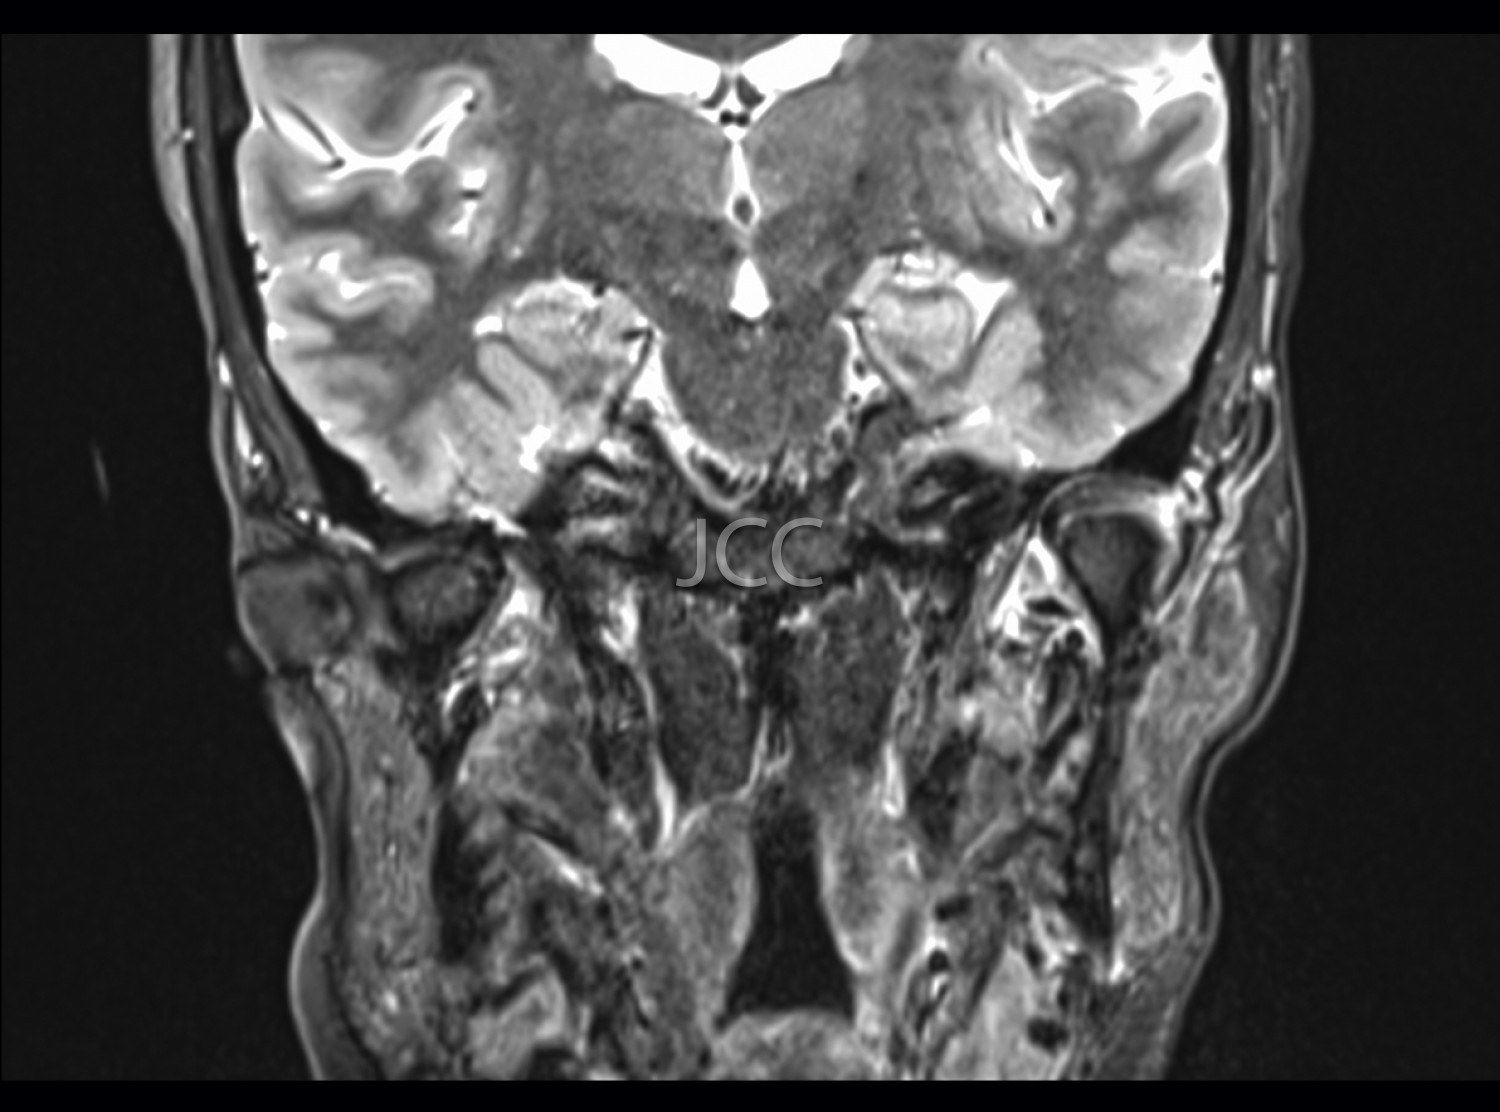

MRI is currently the first-line examination for the study of TMJs pathology. They allow the dynamic study of the relationship of the articular disc and mandibular condyle in the various degrees of buccal opening.